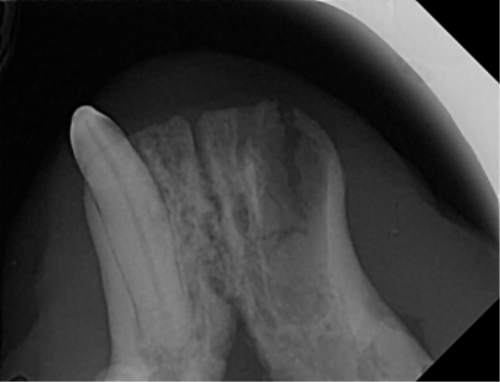

| 치료과정 | -다행히 상추는 금세 포획이 되어서 2번 시도 만에 병원으로 데려갈 수 있었습니다. -많이 마르고 구내염이 꽤 지속된 상태로 보여 검사 후 수술을 진행하기로 했습니다. 방사선, 초음파, 혈액검사를 진행했고 검사상 감사하게도 수술이 가능한 수치가 나왔습니다. 더 못 먹고 염증이 지속될 경우 건강이 더 상할 것 같아 바로 수술을 진행하였습니다. -진통 패치 및 진통제, 항생제 처방을 해주시고 먹는 것을 병원에서 관찰해주셔서 소식을 전해 들을 수 있었습니다. 아이는 첫날 조금밖에 먹지 않았으나 다음날부터 습식에 비벼 준 사료 등을 두 그릇씩 먹으며 씩씩하게 지내주었습니다. 병원 케어를 좀 더 받았으면 하여 일주일 정도 입원을 하였고 피하수액 등을 하여 탈수도 교정이 좀 되었으면 하는 심정이었습니다. -병원에서 마취 상태에서 입 안 사진을 찍어 기록한 후 보여주셨는데 꽤 심각했습니다. 목구멍 쪽 증식한 염증을 많이 절제하였고 레이저 치료까지 진행하였습니다. 치아 엑스레이 촬영도 모두 보내주셔서 기록해두는 데 도움이 되었습니다. -아이가 자발 식이를 잘 할 경우 퇴원을 해도 되기에 집에서 회복 공간을 만들어주었습니다. 나가고 싶은 듯 바깥을 보며 처음에 힘들어했지만 점차 적응하며 편안하게 휴식을 했습니다. 밥은 꼬박꼬박 두 그릇 넘게 챙겨 먹었고 소화가 잘 되는 습식 위주로 주었습니다. 건사료를 언제쯤 먹을 수 있나 관찰하려 두었더니 며칠 안에 금세 먹었습니다. 알갱이 작은 사료를 주었으나 기존에 먹던 맛을 먹고 싶은지 그것만 먹었습니다. |

| 대상묘 치료중 사진 |          |